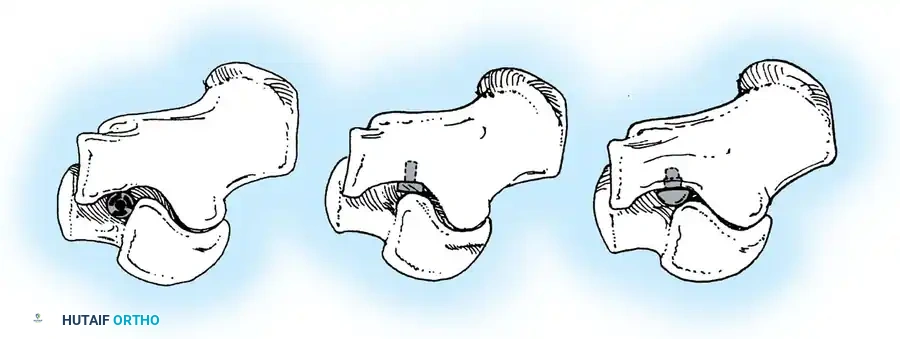

Tarsal Coalition: Pathoanatomy and Genetics

Tarsal coalition is frequently, though somewhat inaccurately, grouped strictly under congenital rigid pes planus. While the anatomical defect is present at birth, symptoms rarely manifest until the cartilaginous bar begins to ossify in late childhood or early adolescence.

Clinical Presentation and Radiographic Evaluation

Ossification Timelines

Because the coalition is initially cartilaginous, the malleability of the peritalar complex prevents significant symptoms in early childhood. As the cartilage ossifies, hindfoot stiffness ensues, and the patient's ability to withstand the microtrauma of vigorous activity declines.

* Calcaneonavicular coalitions typically ossify and become symptomatic between 8 to 12 years of age.

* Talocalcaneal coalitions ossify later, typically between 12 to 16 years of age.

The coalition interface may be bony (synostosis), cartilaginous (synchondrosis), or fibrous (syndesmosis). Paradoxically, incomplete coalitions (cartilaginous or fibrous) are often more symptomatic due to micro-motion at the rigid interface.

Radiographic Imaging

The 45-degree lateral oblique radiograph is the gold standard for diagnosing a calcaneonavicular coalition. The abnormal bar extends from the anterior process of the calcaneus (just lateral to the anterior facet) dorsally and medially to the lateral/dorsolateral extra-articular surface of the navicular. It typically measures 1 to 2 cm in length and 1 to 1.2 cm in width.

In incomplete coalitions, the adjacent bony margins appear irregular, sclerotic, and indistinct. The talar head may also appear small and underdeveloped.

Advanced Imaging and Anatomical Reference Gallery

The following images illustrate various presentations, surgical exposures, and advanced imaging modalities (including CT and MRI correlates) utilized in the comprehensive evaluation and treatment of rigid pes planus and tarsal coalitions: